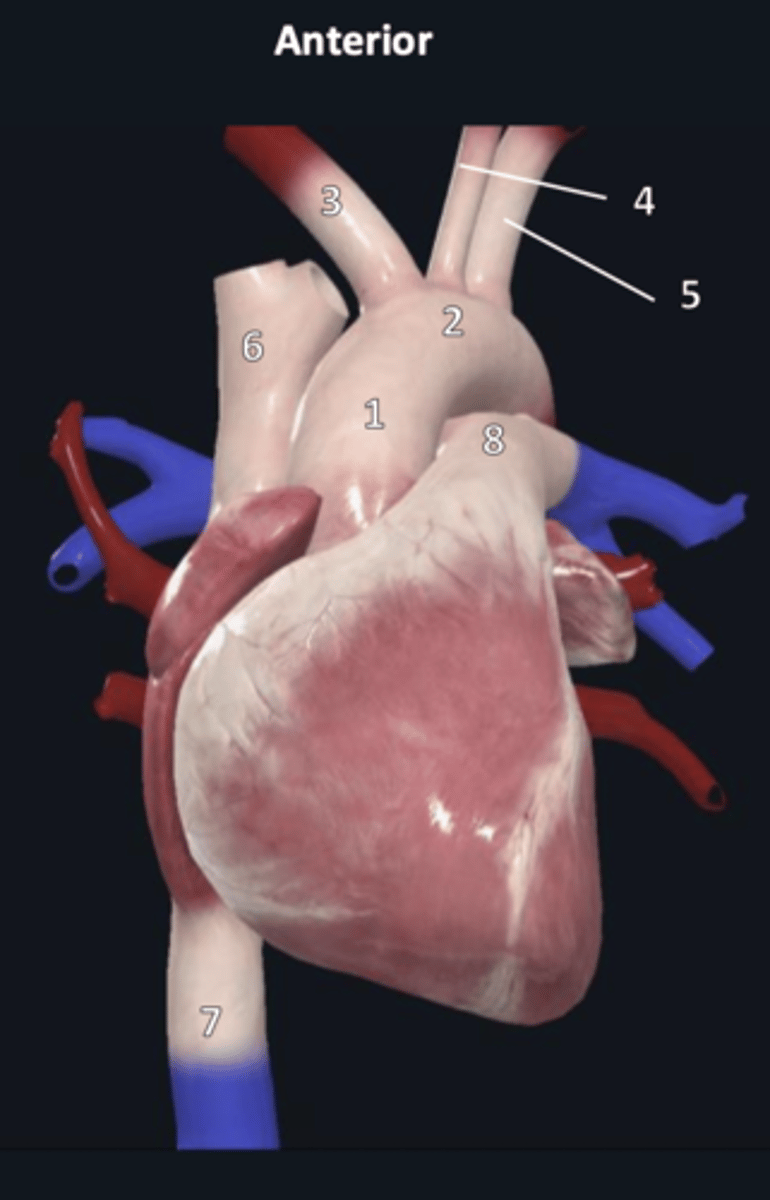

ascending aorta

1

aortic arch

2

brachiocephalic trunk

3

left common carotid artery

4

left subclavian artery

5

superior vena cava

6

inferior vena cava

7

pulmonary trunk

8